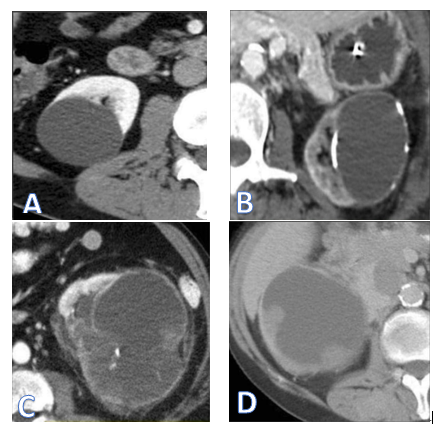

Although there is no agreement on how often and for how long to conduct follow-up, various studies have suggested protocols that involve imaging at the six-month mark followed by annual scans for five years using CT or MRI.2,3,6 By utilizing this monitoring method, literature shows progression rates of IIF lesions in less than 30% of cases (specifically 14.8%, according to O'Malley et al.19 and only 5% in the recent series conducted by Hindman et al.20) These progressions typically occur within a median time frame ranging from 11-18 months based on findings from sources such as research studies numbered (Figure 1).8,18-20

Figure 1 CT images of renal cysts according to Bosniak's classification.

A. Bosniak cysts I B. Bosniak II cyst C. Bosniak III cyst. D. Bosniak IV cyst.